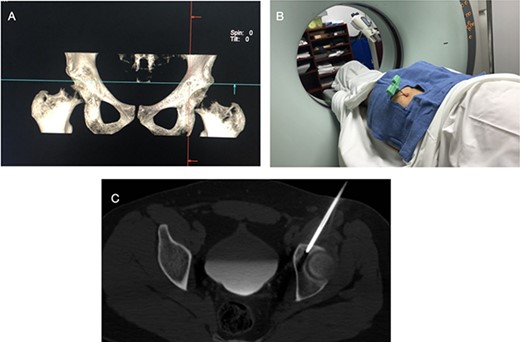

The procedure was made with general anesthesia and in supine position. A 1-cm incision was made for an anterior approach over the hip joint. Careful blunt dissection was done. Percutaneous technique was used with the guidance of a 64 slice Somatom sensation CT scanner (Siemens AG Munich, Germany) with interval cuts of 2 mm to locate the OO. Intravenous contrast was administered to identify the vascular structures at risk (Fig. 3). A 13G × 100 mm bone marrow biopsy needle was used. Image guidance was performed by a senior radiologist (ES). Once the OO was located, accurate insertion of the needle was monitored, and drilling was done manually to help precision in depth (Fig. 4). Multiple bone fragments were obtained and sampled. Immediate image verification showed a space missing the nidus OO. To avoid leaving remnant nidus, curettage was added on the edges and the deep margin of the tumor. Bone samples were sent to histological evaluation and OO diagnosis was confirmed. Wound pain management was administered for 2 weeks and night symptoms disappeared immediately. Complete relief was achieved 3 weeks later. A 12-month follow-up post treatment reported no recurrence of pain and no complications with wound management. ROM and athletic activities are painless. No soft tissue complications were reported.

CT showing the precise site for needle insertion (A), CT control of the needle insertion (B,C).